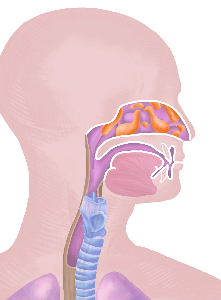

Detailreiche Fotografien aus der medizinischen Praxis ergänzen die Texte; moderne, genaue,

wissenschaftliche Zeichnungen geben Einblick in die Anatomie und die Funktion der Lunge und

anderer Organe.